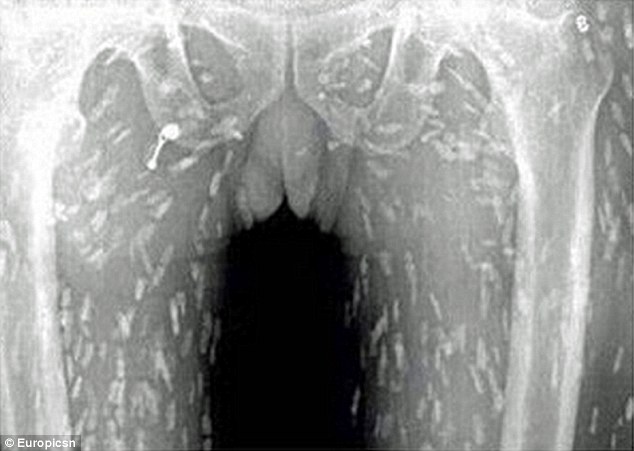

Προς έκπληξη του, οι αξονικές έδειξαν, ότι ολόκληρο το σώμα του είχε μολυνθεί με κυστοειδή σκουλήκια, επειδή έτρωγε πολύ σασίμι- ωμά κομμάτια ψαριού.

Ο άντρας από την Κίνα πήγε στον γιατρό, κάνοντας παράπονα ότι τον πονάει η κοιλιά του και έχει μεγάλη φαγούρα. Προς έκπληξη του, οι αξονικές έδειξαν, ότι ολόκληρο το σώμα του είχε μολυνθεί με κυστοειδή σκουλήκια, επειδή έτρωγε πολύ σασίμι- ωμά κομμάτια ψαριού.

Οι γιατροί πιστεύουν, ότι κάποια από τα ωμά ψάρια ήταν μολυσμένα.

Η μόλυνση από κυστοειδή σκουλήκια εμφανίζεται μετά την κατάποση των προνυμφών του διφαινυλοβαθρίου, που βρίσκονται σε ψάρια γλυκού νερού όπως ο σολομός.

Η κατανάλωση μη μαγειρεμένων φαγητών που είναι μολυσμένα με αυγά κυστοειδών σκουληκιών μπορεί να οδηγήσει σε κυστικέρκωση, όταν τα ενήλικα σκουλήκια μπουν στην κυκλοφορία του αίματος ενός ανθρώπους και μπορεί να αποδειχθούν θανατηφόρα.